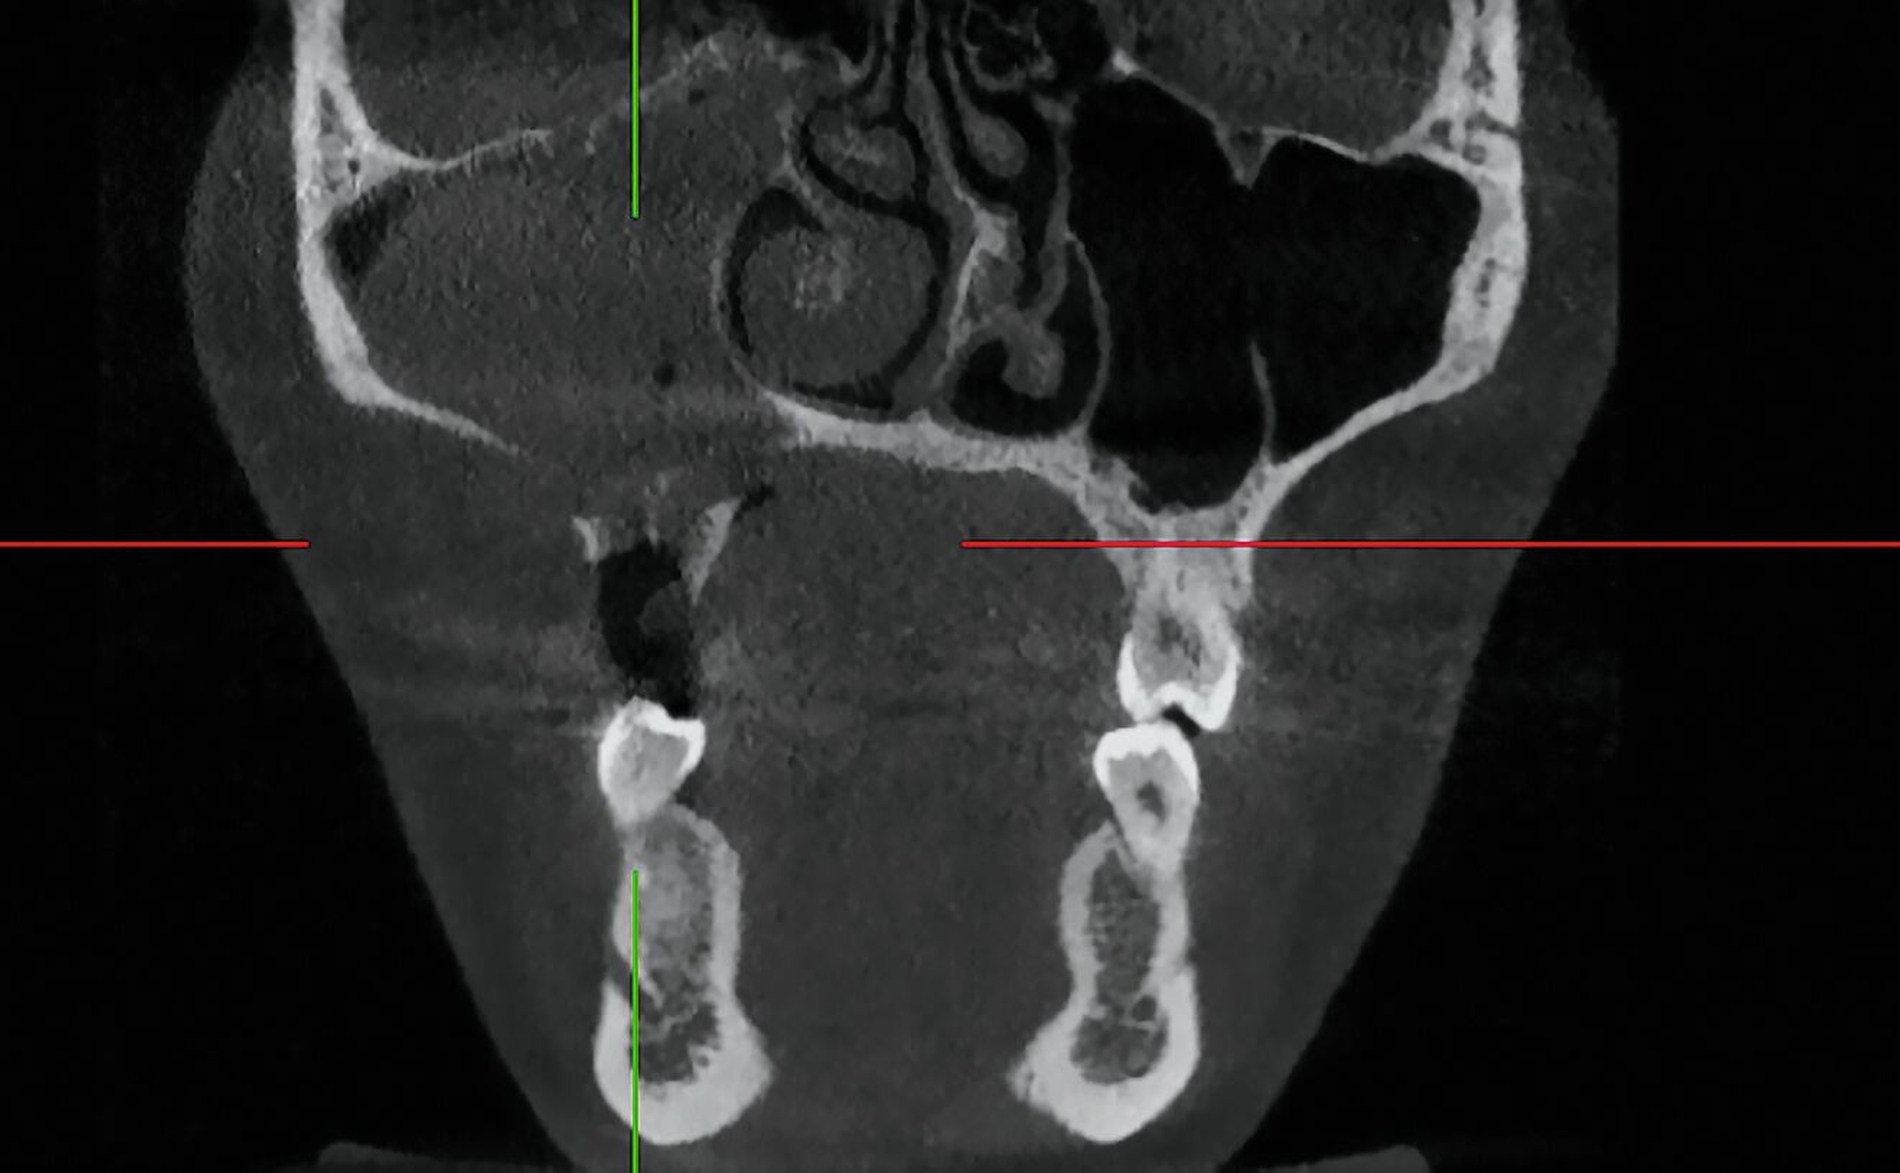

Das DVT zeigte eine Spiegelbildung im rechten Sinus maxillaris, jedoch keinen stark auffälligen knöchernen Befund (Abbildung 2). Die Patientin wurde zu intravenöser Antibiose, Analgesie und Ernährung über eine nasogastrale Sonde stationär aufgenommen. Im Verlauf wurde eine Verbandsplatte per Intraoralscan angefertigt und eine Operation zur Nekrosektomie und Wundanfrischung geplant. Zum Zeitpunkt des operativen Eingriffs hatten sich bereits Teile der vestibulären und der palatinalen Schleimhaut abgelöst. Nach Debridement zeigte sich ein großflächiges Areal mit freiliegendem Knochen. Der Zahn 15 wurde bei Lockerungsgrad III entfernt (Abbildung 3).